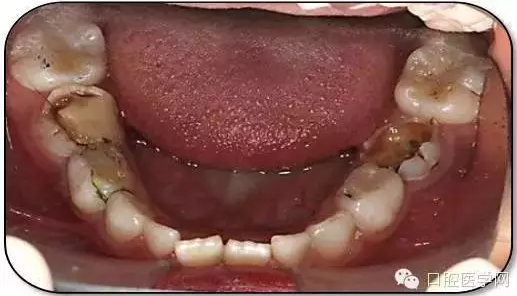

治療結(jié)束后3個月復查

復查:無不適

檢查:口腔衛(wèi)生一般,牙面軟垢菌斑中量。 85O、84DO充填完好,邊緣密合,叩(-),不松,齦無紅腫。

75帶環(huán)絲圈式間隙保持器完好,無松動,無咬合不適。

余牙充填體完好密合,未查及繼發(fā)齲和新發(fā)齲壞。

治療結(jié)束后7個月復查

85O、84DO充填完好,邊緣密合,叩(-),不松,齦無紅腫。X線:84、85根分歧透射影,44、45骨硬板連續(xù),恒牙胚上方骨板厚約2-3mm。75帶環(huán)絲圈式間隙保持器完好,無松動,無咬合不適。64MO中齲。 64MO中齲去腐凈,自酸蝕,SEBOND,樹脂充填。 口腔衛(wèi)生宣教,囑3個月后復診。